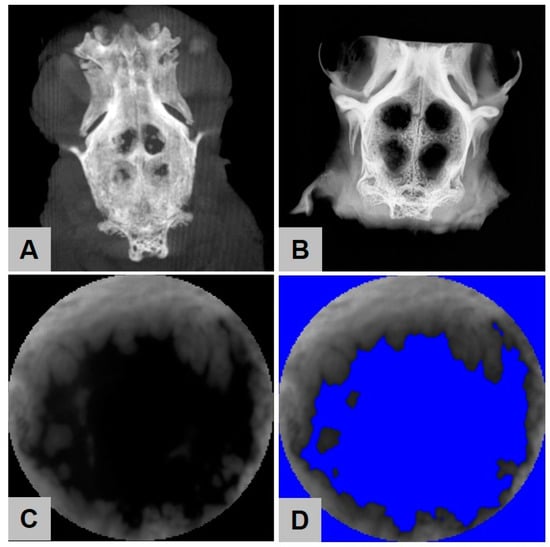

2.4. Digital Volume Tomography (DVT) Analysis

2.5. Contact Radiography